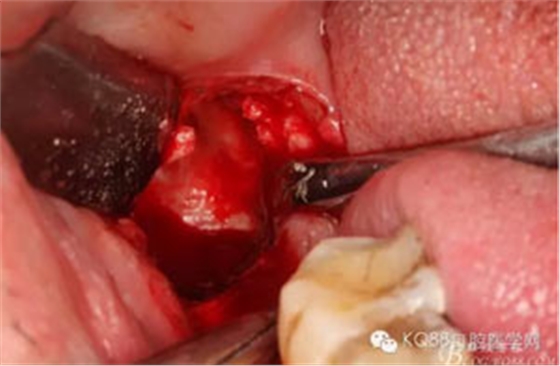

圖7.高速牙鉆去骨。逐漸可見48的牙冠

圖8.刮除牙冠表面的肉芽組織后,可見48 的牙冠